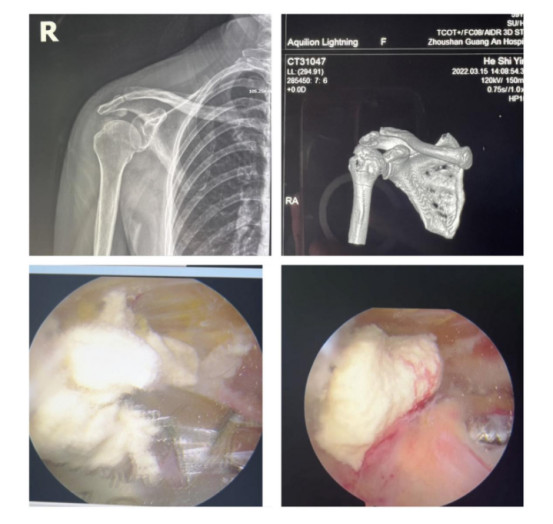

賀大媽慕名來廣安醫(yī)院找羅軍主任就診,面對羅醫(yī)生,賀大媽哭訴:“羅醫(yī)生,我真想剁下自己的這只胳膊。”羅軍主任根據(jù)患者的癥狀拍片,診斷為岡上肌鈣化性肌腱炎,隨后,羅醫(yī)生為李大媽進行了肩關(guān)節(jié)鏡微創(chuàng)手術(shù),竟從她的右肩“擠”出“牙膏”。

鈣化性肌腱炎是一種自限性疾病,就是疾病發(fā)生發(fā)展到一定程度后,經(jīng)長期機體調(diào)節(jié)能夠控制病情發(fā)展并逐漸恢復(fù)痊愈。它分為四個階段:鈣化前期、鈣化形成期、鈣化吸收期、鈣化后期,往往在“鈣鹽斑塊”吸收時,疼痛最劇烈,賀大媽就正處于“吸收期”。

羅軍主任表示,很多人會把肩痛都歸因于肩周炎,這是一個很大的誤區(qū)。其實,肩痛人群中只有15%左右是肩周炎,大部分肩膀疼痛由于肩袖損傷、肩峰撞擊征、鈣化性肌腱炎。而大多數(shù)人也因此認(rèn)為忍一忍就會自愈,常常延誤治療,關(guān)節(jié)鏡微創(chuàng)治療鈣化性肌腱炎,可以快速緩解疼痛,同時可以修復(fù)肩袖損傷,清理肩膀骨刺。